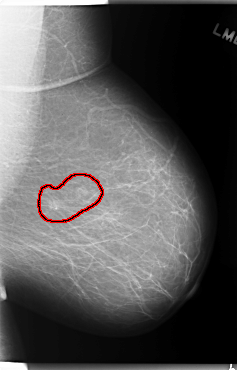

C_0132_1.RIGHT_MLO

FILE: C_0132_1.LEFT_MLO.OVERLAY

TOTAL_ABNORMALITIES 1

ABNORMALITY 1

LESION_TYPE CALCIFICATION TYPE PLEOMORPHIC DISTRIBUTION CLUSTERED

LESION_TYPE MASS SHAPE OVAL MARGINS ILL_DEFINED

ASSESSMENT 4

SUBTLETY 4

PATHOLOGY MALIGNANT

TOTAL_OUTLINES 1

BOUNDARY